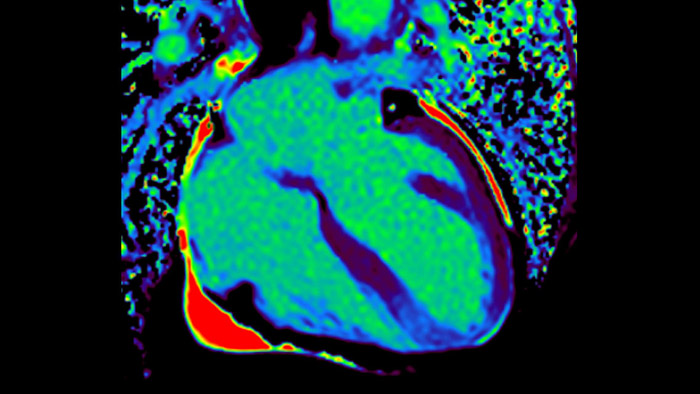

O IntelliSpace Portal MR Caas7,8 Strain9 ajuda no diagnóstico e monitorização do paciente ao proporcionar parâmetros globais de deformação, tais como deformação longitudinal global (GLS), deformação circunferencial global (GCS) e deformação radial global (GRS), utilizando imagens de RM de eixo curto e longo, bem como descrevendo a deformação do miocárdio, como encurtamento, espessamento e alongamento durante o ciclo cardíaco.